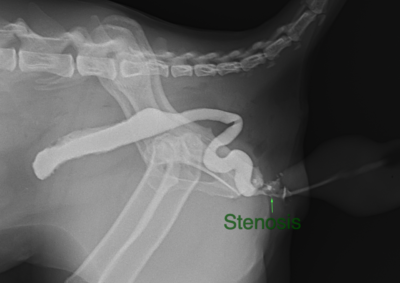

軟部組織外科 注意 ボタンをクリックした先に、治療中および手術中の画像が説明で使用されている場合がございます。 そのような画像に弱い方は閲覧なさらないようお願いいたします。 軟部組織外科 犬の唾液腺切除 軟部組織外科救急・集中治療 猫の腸重積 軟部組織外科呼吸器外科 複数の肺葉捻転 軟部組織外科 肝臓・脾臓過形成病変 軟部組織外科 胆嚢粘液嚢腫 軟部組織外科 尿道狭窄に対する経骨盤尿道瘻設置術 軟部組織外科救急・集中治療 猫の両側尿管閉塞 軟部組織外科救急・集中治療 猫の腸閉塞(毛玉) 軟部組織外科 唾液腺嚢胞 軟部組織外科腫瘍外科 断脚手術(軟部組織肉腫) 軟部組織外科腫瘍外科 猫の肝葉切除術(内側左葉) 軟部組織外科救急・集中治療 腸閉塞・腸切開 <12345678> 症例カテゴリー 放射線治療整形外科軟部組織外科脳神経外科内科腫瘍外科救急・集中治療リハビリテーション科腫瘍内科内視鏡科脳神経科呼吸器外科中医・漢方猫の腎移植循環器科